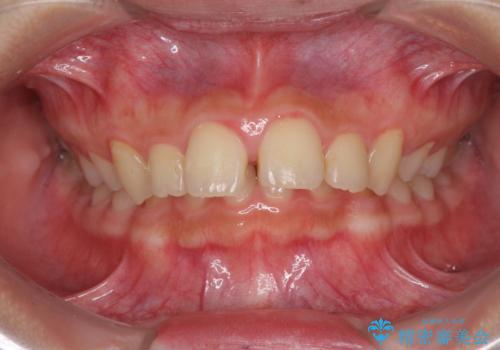

- 深い咬み合わせと上顎前歯の突出感を気にして来院された患者様です。

当院では通常、臼歯の咬合が理想的な位置に対して上顎が前方位にある場合。ワイヤー矯正または補助装置の併用したインビザライン矯正を選択しています。

今回は、できるところまででいいのでインビザライン単体で治療をしたいという希望があったため、インビザラインにて矯正治療を行うこととしました。

正面や横からの写真ではきれいに治っており、患者様は大変満足のいく仕上がりとなりましたが、深い咬み合わせの改善は不十分で、奥歯の咬み合わせも改善させることができませんでした。